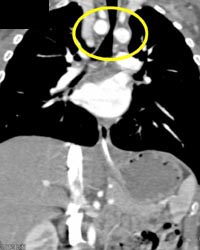

Airway Narrowing Due to Double Arch